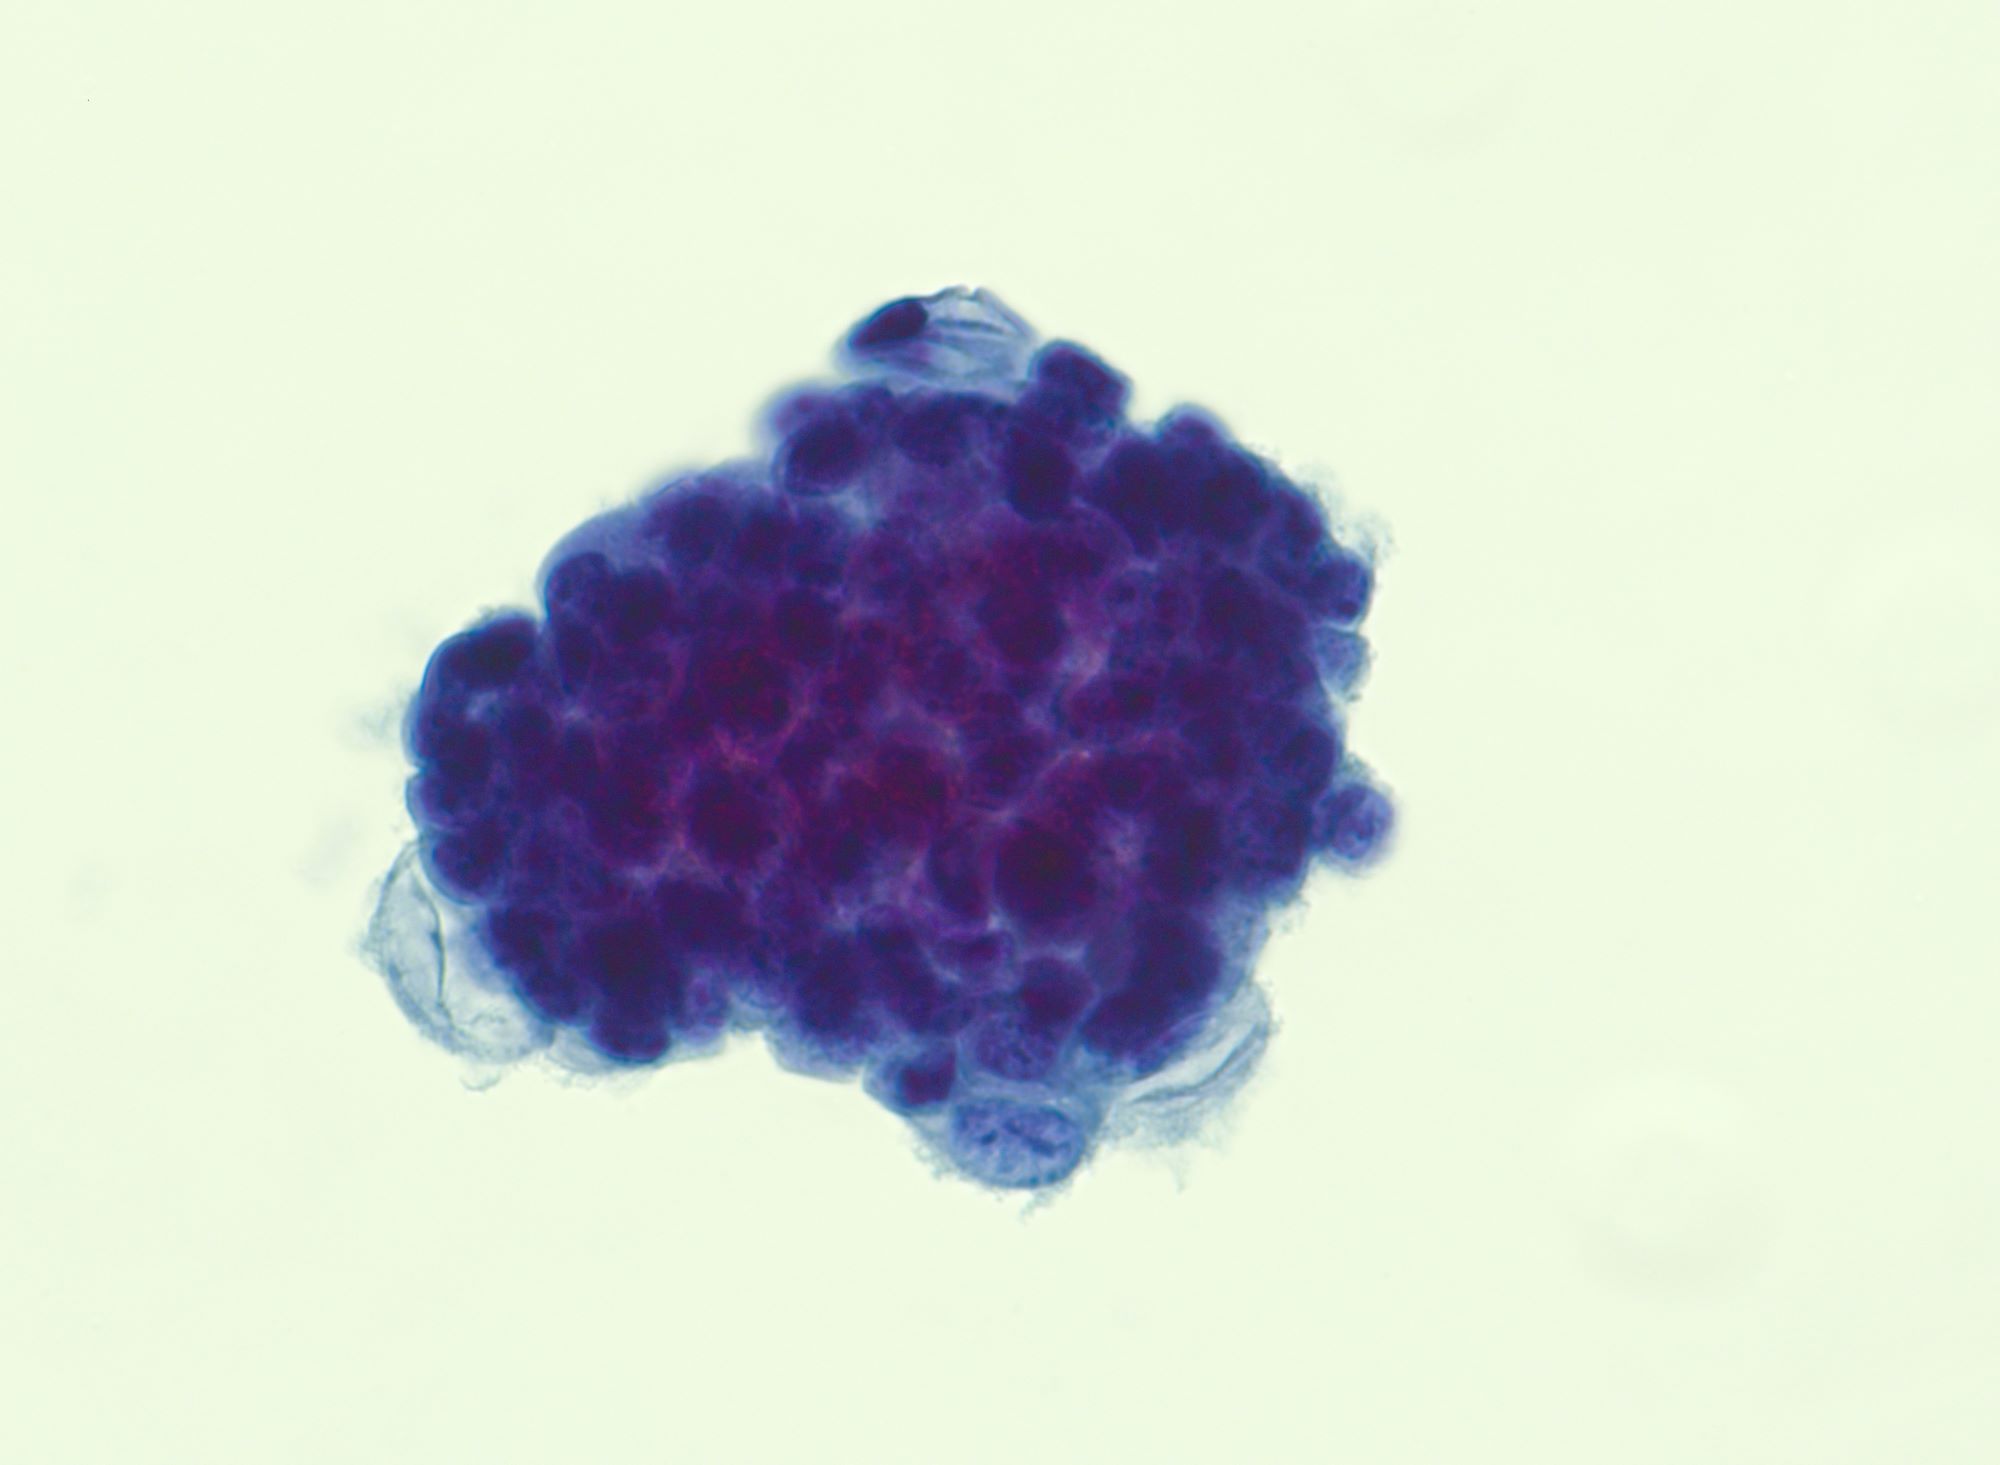

Cytology description

- Malignant glandular cells in clusters and singly

- Moderate amounts of finely vacuolated cytoplasm

- Enlarged hyperchromatic nuclei

- No significant nuclear pleomorphism (< 3x variation in size)

- Prominent nucleoli

Cytology images